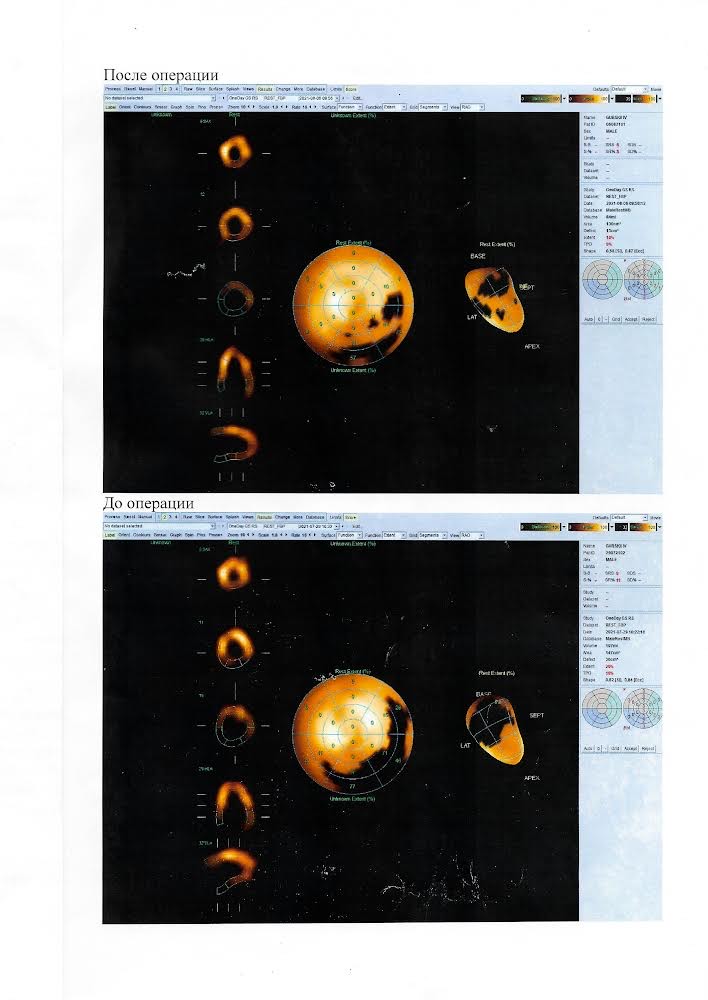

Сотрудники Клиники офтальмологии получили два патента на хирургические методы лечения идиопатического макулярного разрыва.